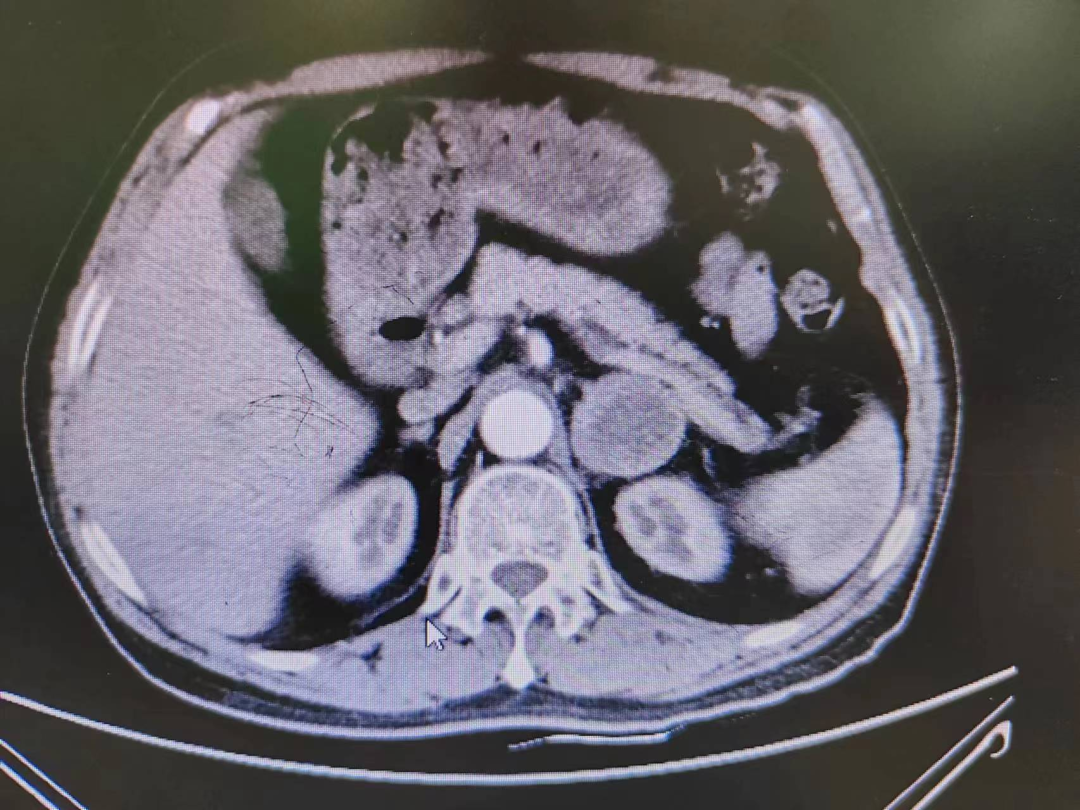

患者熊XX,67歲,因發(fā)現(xiàn)頭暈、頭痛曾多次于外院就診,到新橋醫(yī)院就診完善腎上腺CT考慮嗜鉻細(xì)胞瘤,既往有高血壓病史3年,血壓更高達(dá)230/120mmHg。我院高新區(qū)院區(qū)開(kāi)診后,患者慕名而來(lái)。術(shù)前積極完善血尿兒茶酚胺代謝產(chǎn)物(MNS)均明顯升高,患者于我院高新區(qū)院區(qū)及江南院區(qū)泌尿外科積極控制血壓、心率、血糖,術(shù)前充分?jǐn)U容。

因腫瘤位置位于腎蒂周圍,術(shù)中觸碰腫瘤導(dǎo)致血壓明顯升高,血壓波動(dòng)較大,腫瘤表面血供豐富,不僅需要手術(shù)醫(yī)生豐富的臨床經(jīng)驗(yàn)和高超的技術(shù)水平,也是對(duì)醫(yī)生心理素質(zhì)、勇氣和毅力的嚴(yán)峻考驗(yàn)。

經(jīng)過(guò)泌尿外科醫(yī)師全體討論,在進(jìn)行術(shù)前準(zhǔn)備2-3周后,再次請(qǐng)多學(xué)科討論評(píng)估手術(shù)風(fēng)險(xiǎn),并與患者及家屬充分溝通后于6月30日行腹腔鏡下左側(cè)腎上腺嗜鉻細(xì)胞瘤切除術(shù)。手術(shù)在陳勇主任醫(yī)師的指導(dǎo)下,由孫偉副主任醫(yī)師主刀及王傳麟醫(yī)師完成,術(shù)中見(jiàn)腫瘤與腎蒂血管周圍粘連緊密,與腎動(dòng)脈、腎靜脈分界不清,稍有不慎,可能損傷腎蒂血管可能需要行腎切除術(shù),且分離腫瘤過(guò)程中血壓波動(dòng)較大。但在孫偉精準(zhǔn)操作及分離下,與麻醉醫(yī)生和手術(shù)護(hù)士團(tuán)隊(duì)密切配合,經(jīng)過(guò)2小時(shí)的手術(shù),順利切除嗜鉻細(xì)胞瘤,并保護(hù)好腎臟血管及周圍組織。術(shù)后患者順利出院,術(shù)后血壓及血糖控制良好。